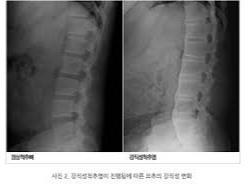

- 자세 변화: 질환이 진행되면서 척추가 굽어 몸이 앞으로 굽는 경향을 보입니다.

- 영상 검사: 엑스레이나 MRI를 통해 척추와 천장관절의 염증 및 손상을 확인합니다.

초기에는 영상검사상 이상이 뚜렷하게 나타나지 않을 수 있으므로, 증상이 지속된다면 반복적인 추적 관찰이 필요합니다.